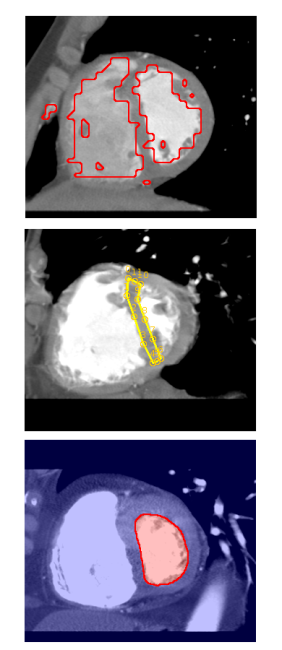

Metoda ta stanowi swego rodzaju uogólnienie klasycznych technik aktywnych konturów stosowanych od dawna w analizie obrazu. Ich zasada jest w gruncie rzeczy dość prosta. Mając obraz, można na nim wskazać różnego rodzaju kontury (o różnym położeniu, rozmiarze, orientacji i kształcie), jednak tylko jeden z nich dokładnie wskazuje miejsce gdzie znajduje się poszukiwana struktura (Rys. 1). Reszta jest w mniejszym lub większym stopniu gorzej dopasowana. Należy zatem znaleźć optymalny, z punktu widzenia danego zadania, kontur. Zaletą takiego podejścia jest relatywna łatwość wykorzystania dostępnej wiedzy eksperckiej. Jednym z ciekawszych sposobów jest wykorzystywanie zbioru przykładów do maszynowego wyuczenia funkcji oceniającej dopasowanie konturu do obrazu.

W aktywnych podziałach, jak już wcześniej wspominałem, zmieniany jest sposób reprezentacji zawartości obrazu ze zbioru pikseli na zbiór mniejszej liczby bardziej złożonych elementów. W swoich badaniach rozważałem między innymi: odcinki, elipsy i tak zwane super-piksele (małe jednolite obszary) (Rys. 2). Ta zmiana powoduje, że pojęcie konturu, intuicyjnie oczywiste w przypadku reprezentacji opartej o piksele, nie może być zastosowane. Dlatego zamiast optymalnego konturu poszukiwany jest optymalny podział zbioru elementów na te, które identyfikują poszukiwaną strukturę i te, które stanowią tło.

W celu pozyskania danych i wiedzy medycznej nawiązana została współpraca z lekarzami radiologami: z dr. Michałem Podgórskim, obecnie zatrudnionym w Instytucie Centrum Zdrowia Matki Polki w Łodzi oraz z dr Izabelą Michalską pracującą w Uniwersyteckim Szpitalu Klinicznym im. N. Barlickiego w Łodzi. Dzięki tej współpracy udało się stworzyć cztery bazy obrazowań medycznych: obrazy RTG ręki dzieci (wykonywane pod kątem diagnostyki wieku kostnego), obrazy MR ośrodkowego układu nerwowego (diagnostyka stwardnienia rozsianego), obrazy MR kolan (diagnostyka zmian chrząstki stawowej) oraz obrazy CT brzucha (wykrywanie zmian w trzustce). Każda z tych baz zawiera 100 reprezentatywnych obrazowań. Na każdym z nich, z wykorzystaniem systemu PLANTATION, radiolodzy zaznaczyli, wykonując ogromną pracę, od jednej do kilkunastu struktur istotnych z punktu widzenia diagnostycznego. Za przykład ilustrujący ilość tej pracy może posłużyć oznaczenie samej trzustki, które zajmowało 2 godziny dla jednego pacjenta (oznaczane były wszystkie przekroje trójwymiarowego badania CT).